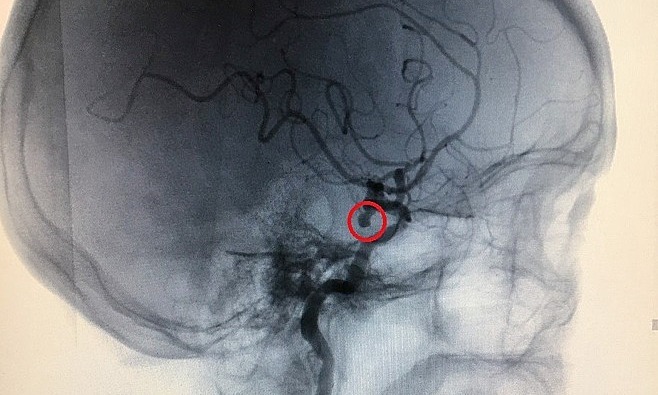

Ông khuyến cáo, các bác sĩ cần can thiệp sớm để loại bỏ túi sưng, không chờ các triệu chứng bất thường để tránh nguy cơ vỡ dẫn đến xuất huyết não, đột quỵ, tử vong. GS Nguyễn Huy Thắng, Phó chủ tịch Hội đột quỵ Việt Nam kiêm trưởng khoa bệnh lý mạch máu não Bệnh viện Nhân dân 115 TP.HCM, cho biết giống như anh chàng này, nhiều bệnh nhân lo lắng, ‘bỗng biết mình là một bệnh nhân nhỏ. Phình mạch não, muốn biết có nên can thiệp sớm không. — Theo giáo sư Đường, túi phình động mạch não rất phổ biến, ước tính chiếm 2-3% dân số, tỷ lệ người cao tuổi có thể cao hơn nữa. Vì vậy, ở Việt Nam, ước tính có khoảng 2 đến 3 triệu quả “bom nổ chậm” trên 100 triệu dân.

ISUIA (Nghiên cứu Quốc tế về chứng phình động mạch nội sọ) được coi là chứng phình động mạch não không gián đoạn lớn nhất cho đến nay. 1.692 trường hợp phình mạch từ 2 mm trở lên đã được điều trị, trong đó có 1.077 người có kết quả hoàn toàn. Trong 5 năm, không có ai bị vỡ túi phình nhỏ hơn 7 mm ở tuần hoàn trước và nguy cơ vỡ túi phình động mạch chủ sau cao hơn. Tỷ lệ này chiếm khoảng 1,5% vào giữa năm. Nếu túi phình khoảng 7-12mm, đặc biệt khi lớn hơn 12mm thì sk vỡ sẽ tăng lên.

Hiện nay, có 3 lựa chọn để can thiệp túi phình động mạch não không gián đoạn, bao gồm phẫu thuật kẹp túi phình, can thiệp đóng túi phình, điều trị bảo tồn. Hai nghiên cứu phân tích tổng hợp đánh giá kết quả của phẫu thuật kẹp túi phình không gián đoạn, và nhận thấy tỷ lệ tàn tật là 4,1% và 10,9%, và tỷ lệ tử vong là 1% và 2,9 tương ứng là%. Nguy cơ tử vong do phình mạch tuần hoàn sau hoặc phình mạch lớn có thể lớn hơn 20%.

Sau can thiệp bít túi phình, nghiên cứu cho thấy kết quả bất lợi của 3 nhóm can thiệp là 4%; 3 can thiệp Các nhóm Kết quả kém, tỷ lệ tử vong là 1-2% Trong nghiên cứu ISUIA, tỷ lệ tử vong ở nhóm can thiệp là 3,1%. Có túi phình tuần hoàn hoặc túi phình lớn hơn ở phía sau và nguy cơ tử vong là cũng cao hơn. -Điều trị thận trọng bao gồm kiểm soát huyết áp, tránh hút thuốc và uống rượu. Điều quan trọng là theo dõi túi phình bằng kỹ thuật chụp mạch không xâm lấn (như MRA hoặc CTA) sau 6 tháng hoặc một năm để đánh giá sự gia tăng kích thước khối u. Theo dõi. Nếu bạn là lần đầu tiên chọn MRA. Nên lặp lại MRA sau để tránh sai sót giữa hai phương pháp này Đối với những túi phình còn nguyên vẹn nhỏ hơn 7 mm thì đây là lựa chọn hợp lý. Túi có độ nhô ra từ 7 đến 12 mm Nên thận trọng vì hiện nay không có bằng chứng cho thấy can thiệp tốt hơn điều trị bảo tồn. Bệnh nhân trong nhóm này nên được theo dõi kích thước túi phình 6 tháng một lần. Quyết định bắt đầu can thiệp sớm phụ thuộc vào các yếu tố liên quan, chẳng hạn như tuổi, tiền sử gia đình, cơ địa của túi phình, Tăng kích thước,… Hiện chưa có bằng chứng cho thấy việc sử dụng kháng sinh, tập tiểu cầu và chống đông làm tăng nguy cơ vỡ túi phình, do đó, bác sĩ Thắng cho biết, không nên loại bỏ những loại thuốc này, hầu hết các trường hợp là túi phình bảo tồn. Khuyến nghị đối với các nhóm đối tượng có nguy cơ cao, chẳng hạn như gia đình có người nhà bị vỡ phình mạch và bệnh nhân thận đa nang. – Lê Phương